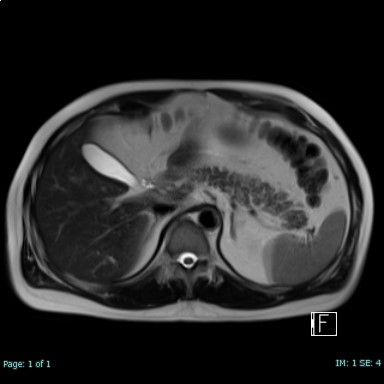

腹部MRCP検査

腹部MRCP検査のMRCPとはMagnetic Resonance Cholangiopancreatographyの略で、MRI装置を用いて胆嚢や胆管、膵管を同時に描出する検査です。

胆石、胆管結石や膵臓に関しては嚢胞性病変(IPMNなど)、膵臓の嚢胞性腫瘍の検出、膵管及び分岐膵管の拡張・狭窄・途絶、膵臓の萎縮の評価に特に優れています。